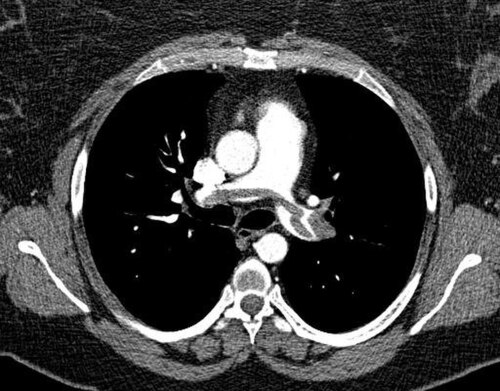

CT Angiography — Massive Pulmonary Embolism

CT angiography showing massive pulmonary embolism with complete occlusion of the pulmonary artery

CT Downloaded 2026-03-15

Ct

Cta Pulmonary 120 kVp W:350 L:50

Wikimedia Commons: CTA Chest With Massive Pulmonary Embolism and Complete Occlusion.jpg